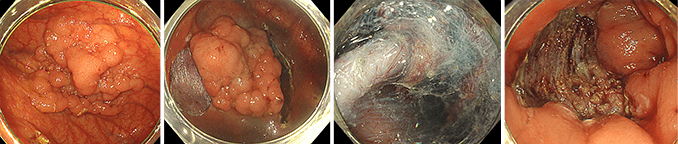

良性のポリープやがん化のリスクがある病変に対して、スネアという金属の輪になった器具(スネア)で病変を締め付けて切除します。

早期がんやその疑いのある腺腫に対して、電気メスを用いて病変を含む粘膜とその下の層で一括に切除する方法です。EMRに比べて、大きな病変を深い層で切除でき、より確実な切除が可能です。

早期大腸癌に対するESD